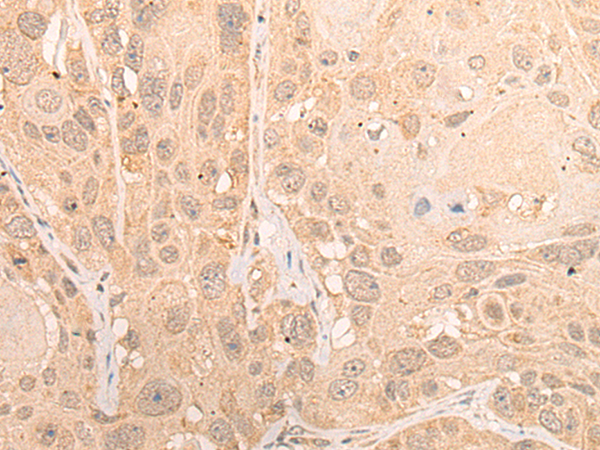

分类: 科研抗体货号: P13206别名:应用: IHC反应种属: Human, Mouse, Rat